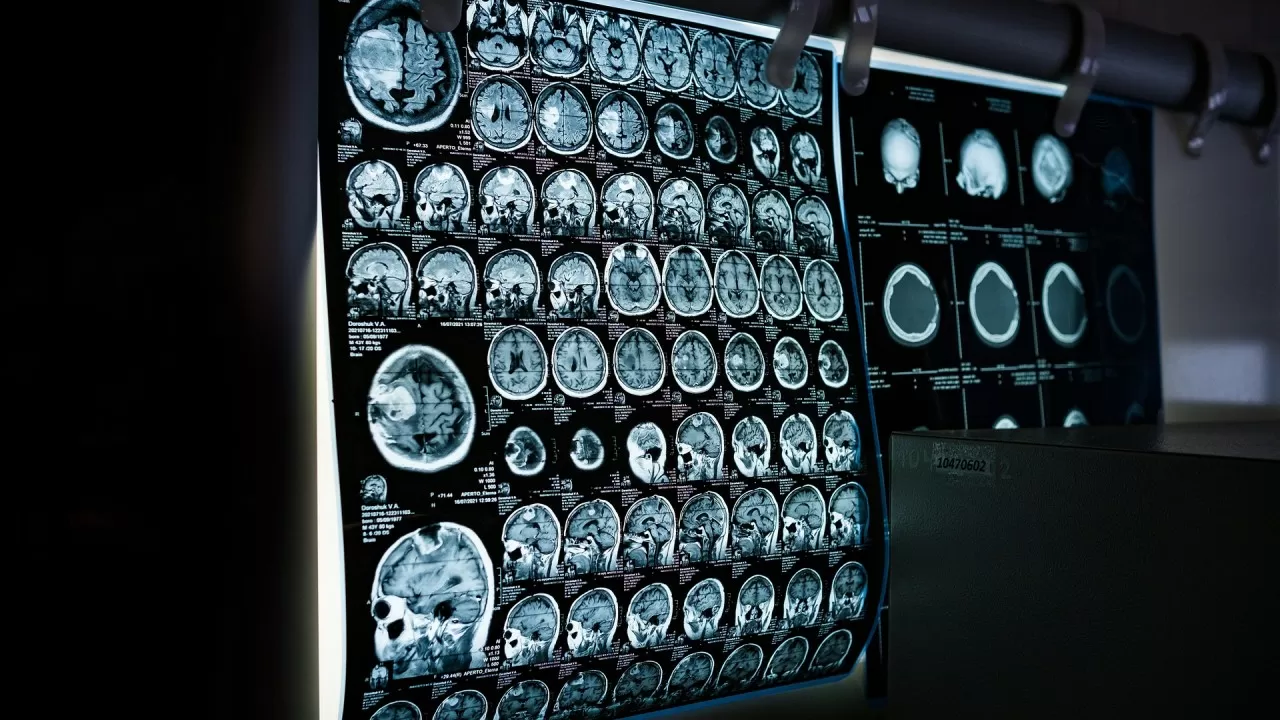

Причину смерти в Казахстане будут выявлять по КТ Фото: pixabay.com

Основной целью предлагаемых изменений является внедрение и использование судебно-медицинскими экспертами современных неинвазивных методов исследования при установлении причины смерти. В их числе ключевое место отводится компьютерной томографии, которая позволяет получить детальную визуализацию внутренних органов и повреждений без проведения традиционного вскрытия.

Применение компьютерной томографии в судмедэкспертизе широко используется в международной практике и рассматривается как важный инструмент повышения точности и объективности исследований. КТ позволяет выявлять скрытые травмы, внутренние кровоизлияния, повреждения костей и органов, а также фиксировать данные в цифровом виде для последующего анализа и хранения.